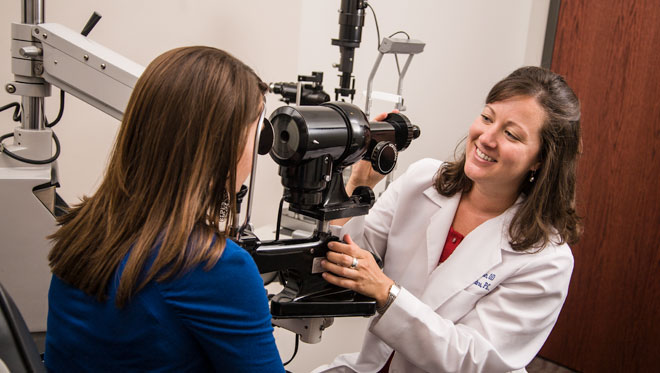

Examen de la óptica es gratuito para todos. Y la lente y el armazón tenemos muchas marcas y muy economico. Sólo visítenos y disfrute de su cita con nuestro médico óptico